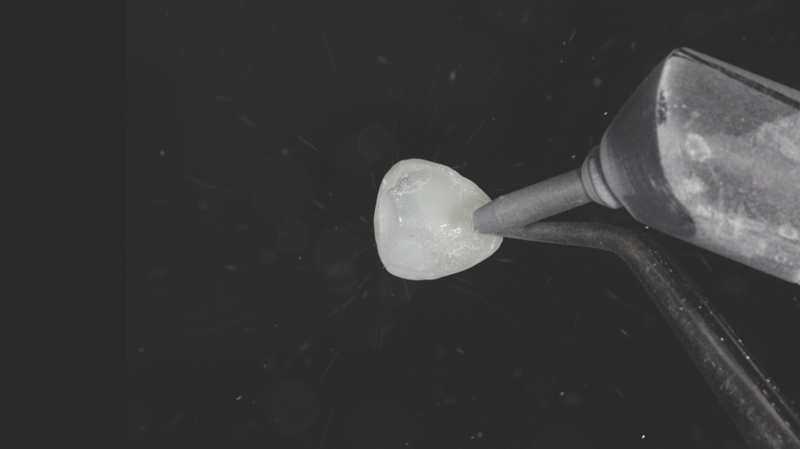

- Internal Surface Preparation: Air abrasion was performed on the internal surface of the veneer. Alternatively, Ultra-Etch™ 35% phosphoric acid can be used for this step.

- Adhesive Coating: The internal surface was coated with Peak™ Universal Bond adhesive.

- Adhesive Thinning and Curing: The adhesive was air thinned, then light-cured using the VALO™ X curing light for three seconds on Xtra Power mode.